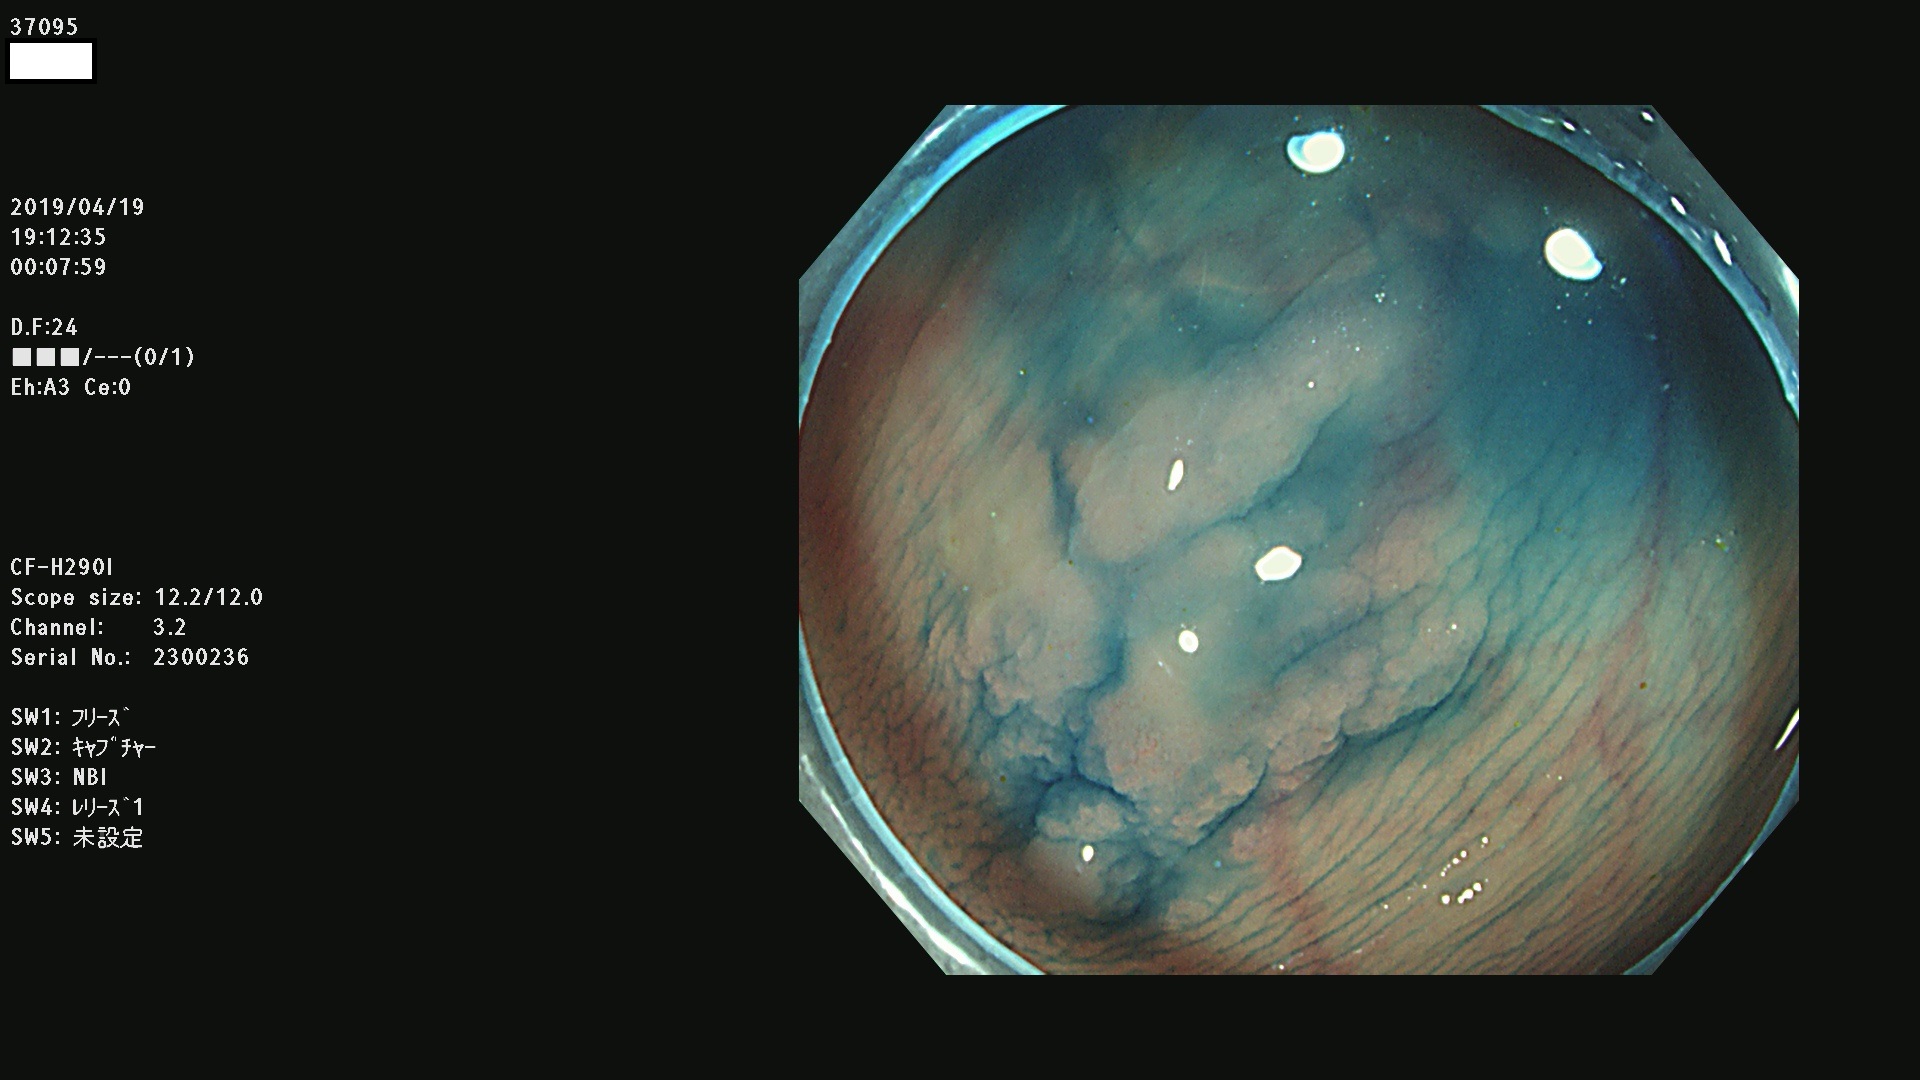

37000 37002 37004 37005 37006(SSAPのみ) 37007 37009 37013 37014 37015 37017(SSAPのみ) 37019 37020 37021 37022 37025 37026 37027 37028 37029 37031 37032 37033 37034 37035 37036 37037 37038 37041 37042 37043 37044 37045 37047 37051 37052 37053(SSAPのみ) 37055 37056 37058 37060 37061 37062 37063 37067 37072 37073 37074 37076 37077 37078 37079 37080 37081 37083 37084 37085(SSAPのみ) 37086 37087 37088 37089 37092 37093 37094 37095 37097 37098 3709

発見困難で危険性の高い平坦型病変(上記100名より抽出)